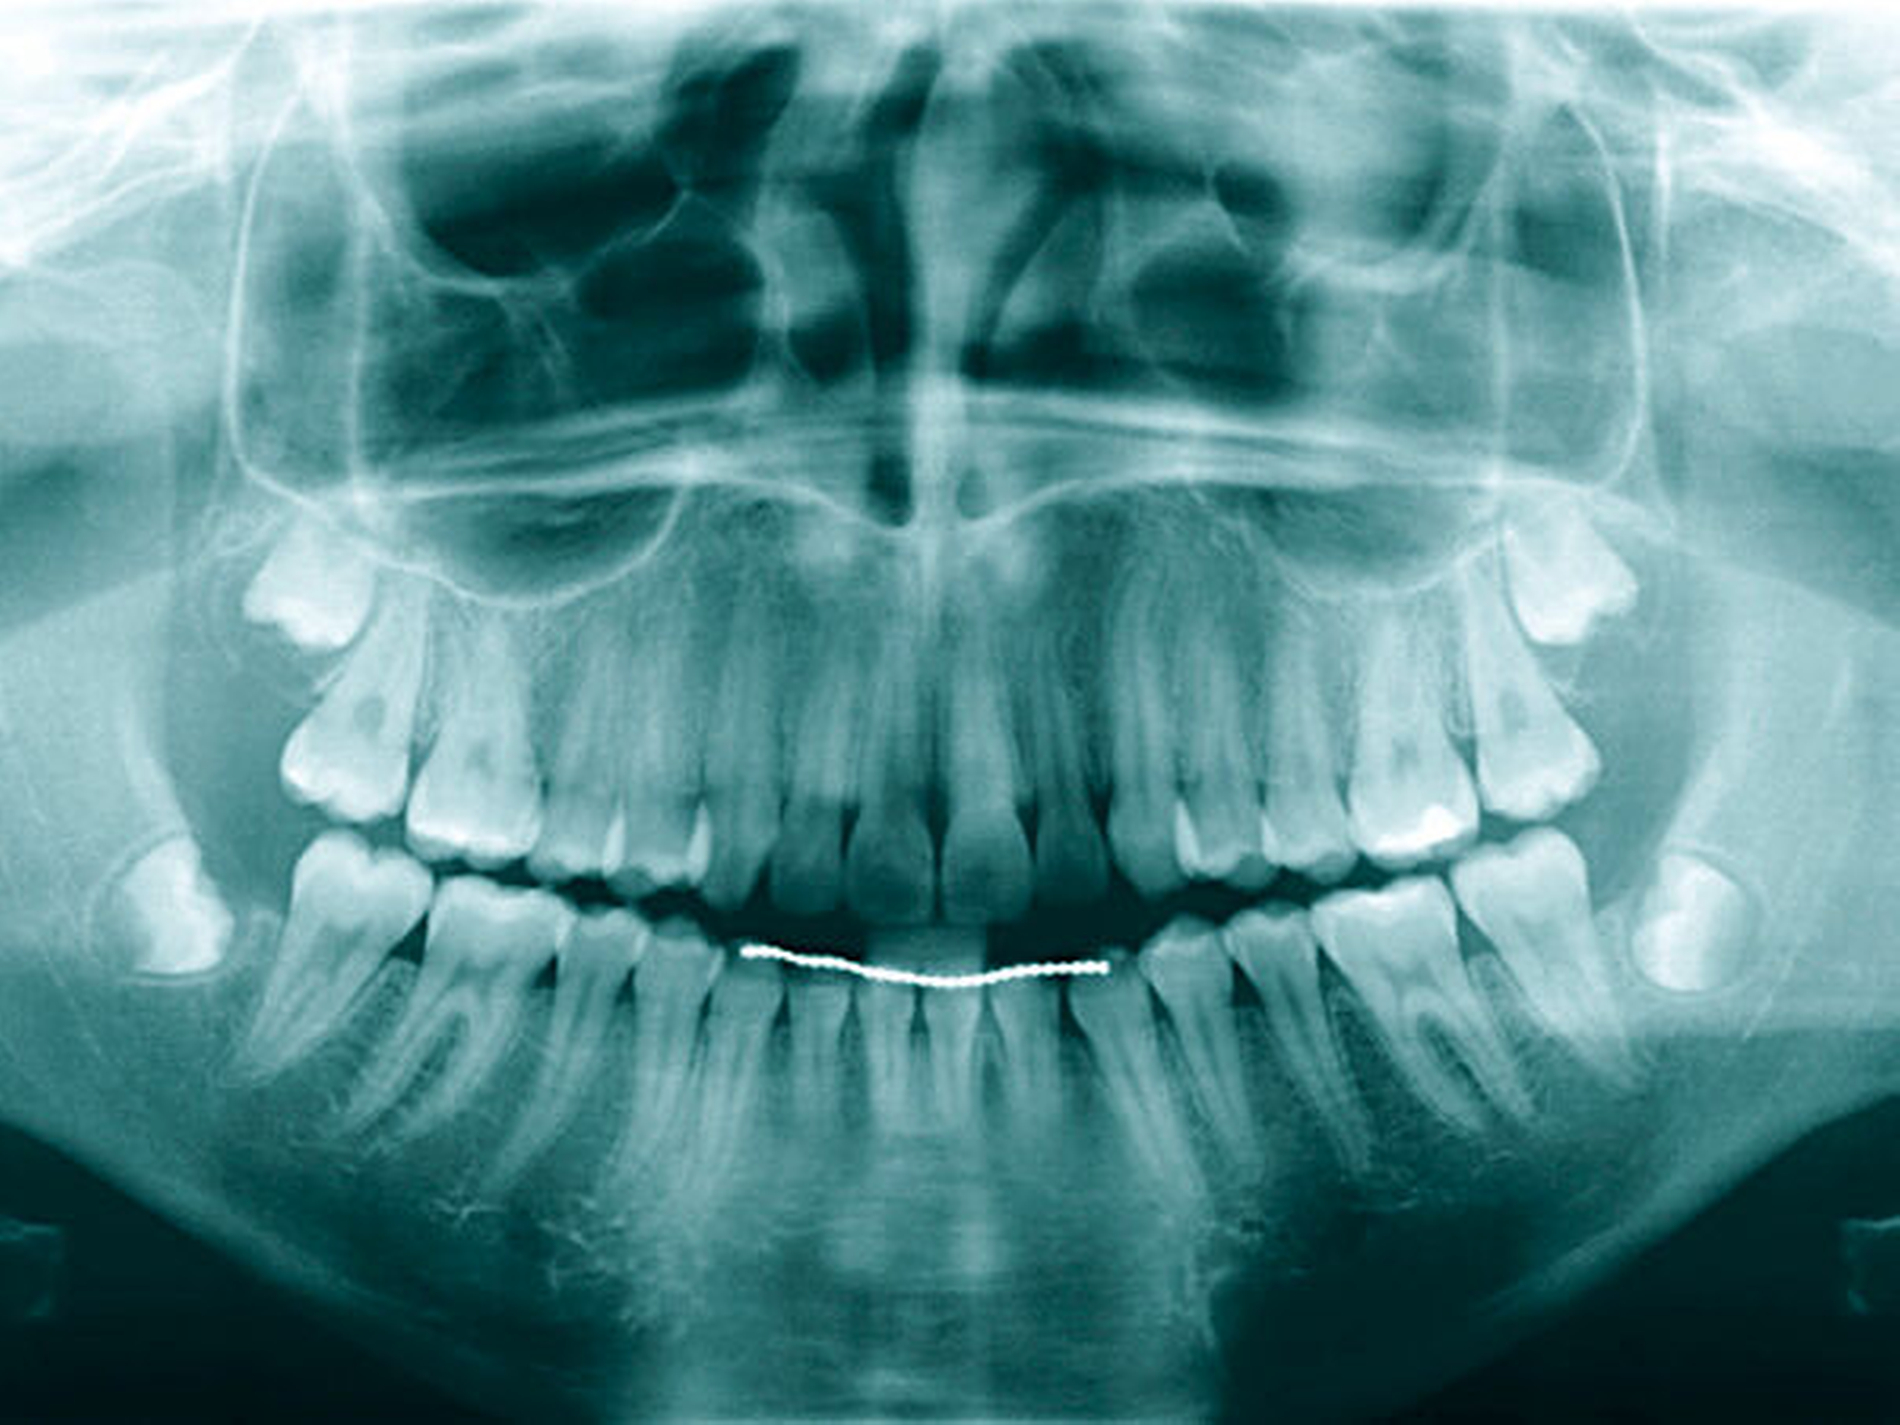

Auch bei scheinbar nicht optimalen Grundvoraussetzungen – wie einem zu erwartenden nicht ganz idealen Kronen-Wurzel-Verhältnis (1:1) – scheint die kieferothopädische Extrusion als Behandlungsoption nicht direkt ausgeschlossen werden zu müssen. Auf dem im Fall gezeigten OPG (Abbildung 9) stellen sich die Zahnwurzeln von 14 und 15 im kontralateralen Vergleich deutlich kürzer dar als die der Zähne 24 und 25. Die elektronische Messlänge bei der Revision der endodontischen Behandlung von Zahn 15 vor Eingliederung des Langzeitprovisoriums betrug lediglich 12 mm. Dennoch wiesen die Zähne 14 und 15 nach der Retentionsphase keine Lockerungsgrade auf, sodass die Autoren in der vermeintlich geringen Wurzellänge keine unbedingte Kontraindikation für das Ziel der Zahnerhaltung sehen. Auch wenn in diesem Fall die unterschiedliche Zahnlänge der Prämolaren im kontralateralen Vergleich klar mit der Extrusion der Zähne 14 und 15 zu erklären ist, stellen kieferorthopädische Bewegungen auch eine mögliche Ursache für die Verkürzung von Zahnwurzeln durch Resorptionen dar.